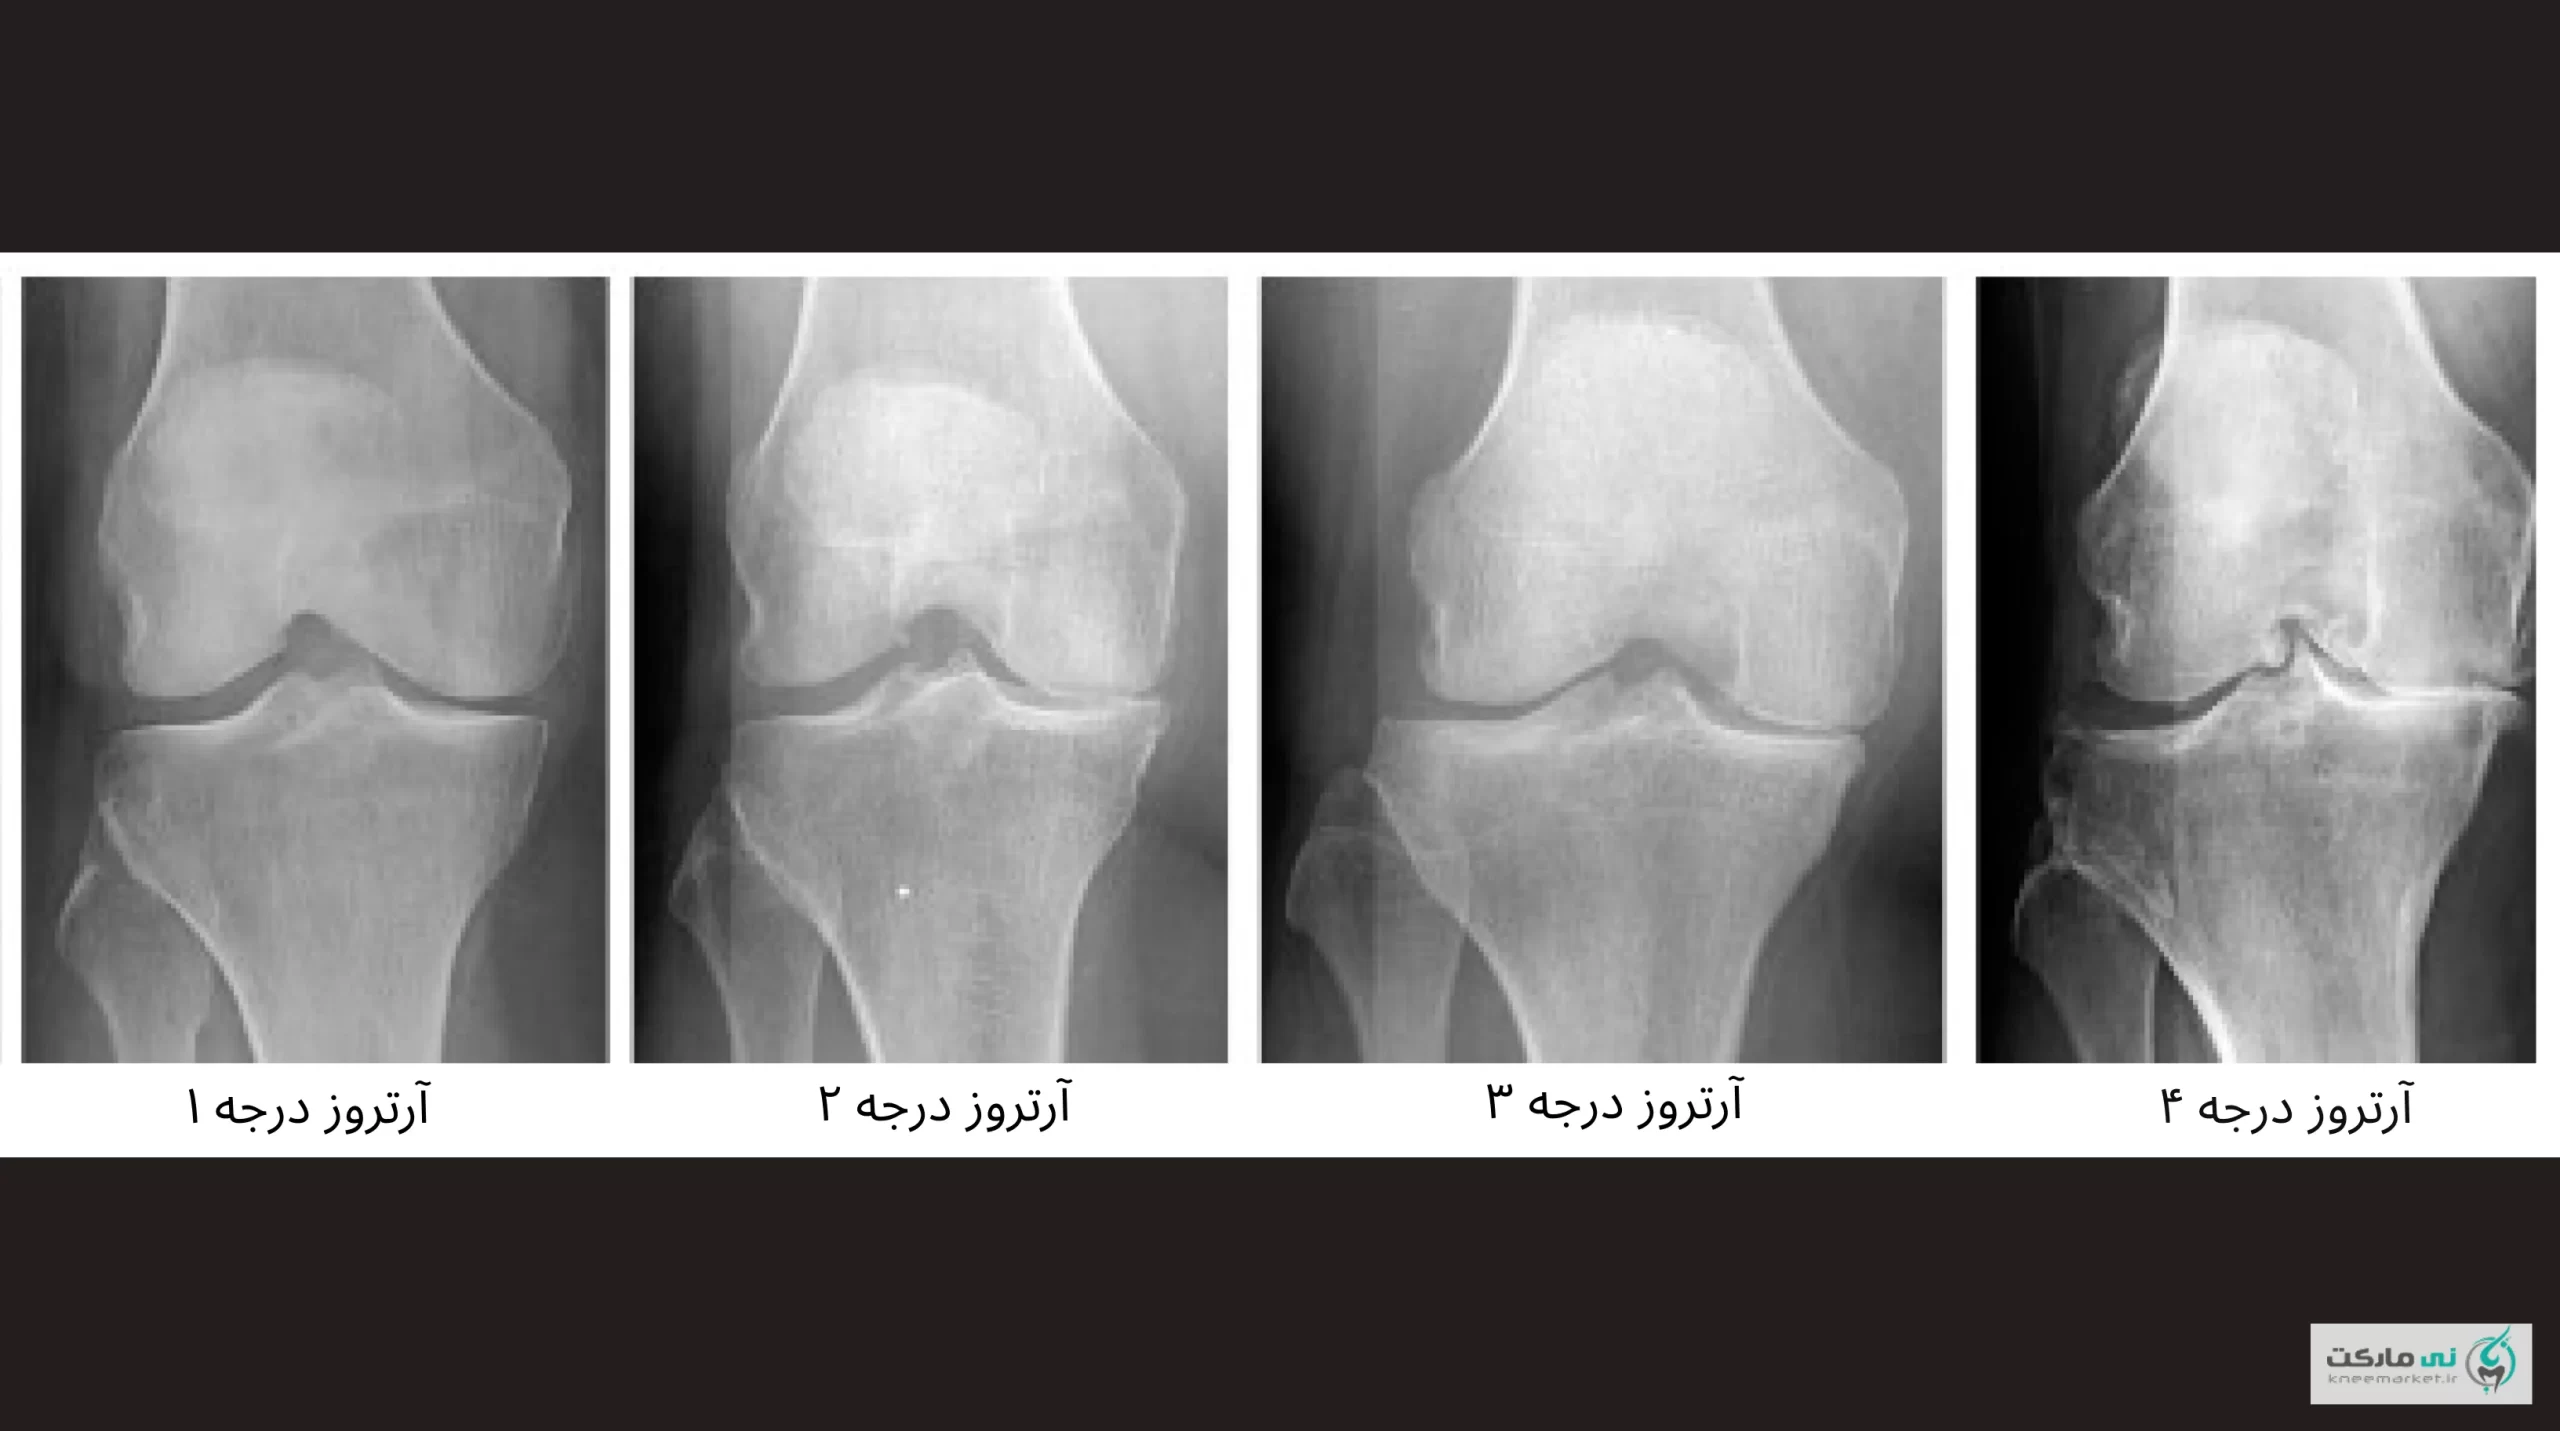

درمان آرتروز زانو بر اساس شدت

اما بهطورکلی درمان آرتروز زانو بر اساس شدت آسیب، درجه یا گرید، و علائم آن تعیین میشود.

وقتی غضروف بهطور کامل از بین رفته و درد حتی در حالت استراحت وجود دارد (آرتروز پیشرفته، گرید ۴)، جراحی تعویض مفصل تنها راه بازگشت عملکرد طبیعی است.